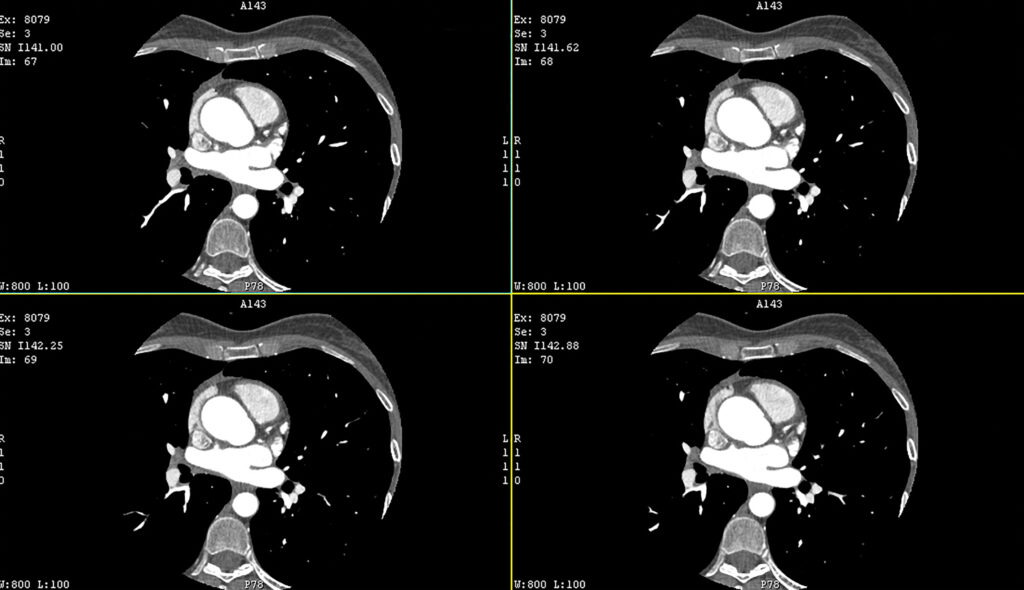

Photon-counting detector CT (PCD-CT) technology has emerged as a promising advancement in cardiac imaging, offering high spectral resolution, reduced noise, and improved contrast-to-noise ratio compared with conventional energy-integrating detector CT (EID-CT). This study by Mergen et al., published in Insights into Imaging (August 2025), evaluates the feasibility of late enhancement (LE) PCD-CT for left ventricular myocardial characterisation in patients with ventricular arrhythmias, using invasive electroanatomical mapping (EAM) as the reference.

LE PCD-CT scans, acquired five minutes after contrast administration, enabled calculation of myocardial extracellular volume (ECV) directly from iodine maps, avoiding the need for separate unenhanced scans and registration. The authors introduced atlas maps—a novel visualisation combining colour-coded ECV data with myocardial wall thickness—to identify fibrosis, scar, and myocardial thinning in a single display.

Image quality was high overall, with only 3% of myocardial segments in ischaemic and 2% in non-ischaemic cases excluded due to beam-hardening artefacts from CIEDs. In ischaemic cases, myocardial thinning was the predominant abnormality, whereas elevated ECV dominated in non-ischaemic disease.